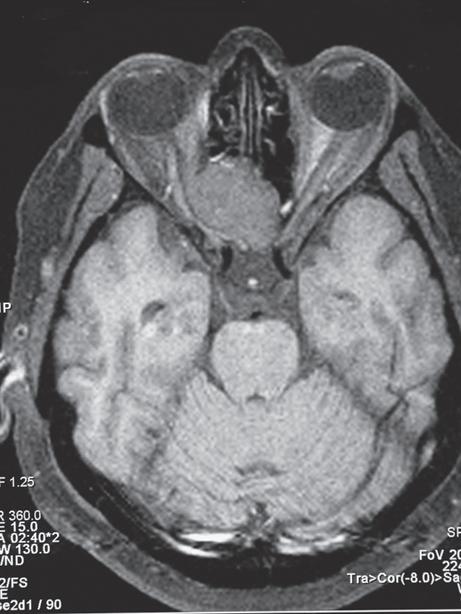

1.5 Not all chronic optic neuropathy with a “cupped” disc is glaucoma! This 48-year-old patient asked her optometrist for a change of glasses because of blurred vision. The optometrist found A, B visual acuity right 20/30, left 20/60, intraocular pressures of right 25, left 29, and bilateral disc “cupping”, and referred the patient to an ophthalmologist for treatment of possible glaucoma. Perimetry was attempted but fields were said to be “unreliable”; the ophthalmologist commenced glaucoma eyedrops. One year later, visual acuity had decreased further to right 20/60, left 20/200, and optic disc pallor was noted; C MRI revealed a large suprasellar meningioma. Visual outcome would probably have been better with earlier diagnosis. For how to safely diagnose glaucoma, see p. 37.

Bilateral disc swelling

10. Bilateral disc swelling could be papilledema (disc swelling due to raised intracranial pressure). The first investigation should be urgent (same-day) magnetic resonance imaging (MRI) plus magnetic resonance venography (MRV) to exclude a brain tumor or dural venous sinus thrombosis (see p. 120) (Fig. 1.10).

1.10 This 38-year-old man presented to an ophthalmic emergency department complaining of blurred vision and headaches. Examination revealed visual acuity 20/20 right and left and bilateral moderate disc swelling A, B. Because vision was good and there were “no other neurologic signs”, the patient was allowed to go home and was scheduled for neuro-imaging as an outpatient. Two days later, while driving, the patient experienced a generalized seizure, resulting in severe injuries to himself and another driver. MRI revealed a brain tumor which was found at surgery to be an astrocytoma. For how to safely manage disc swelling with normal vision, see p. 110.